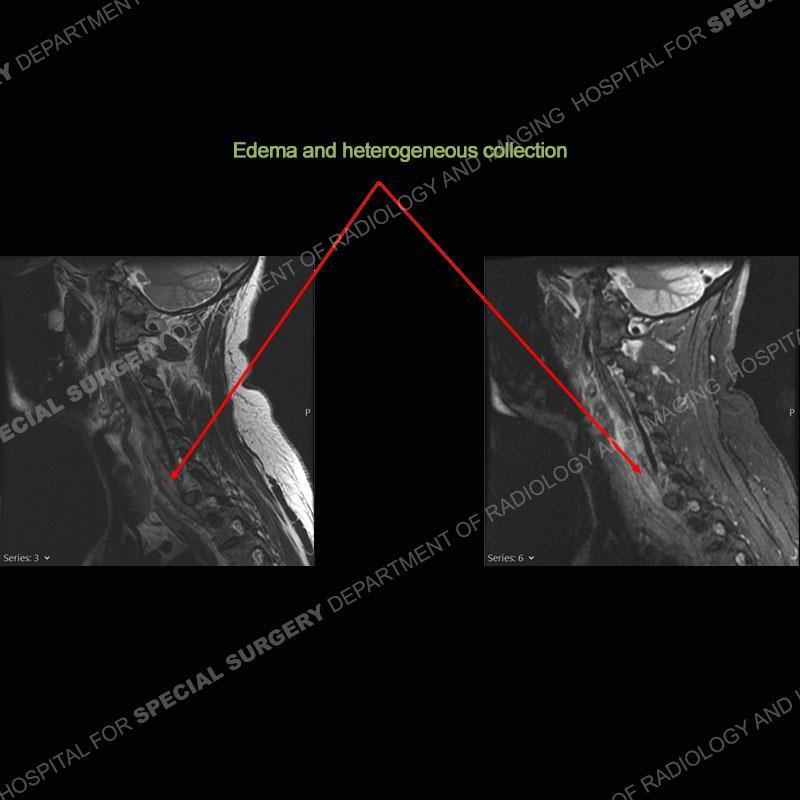

The radiographs demonstrate a prevertebral soft tissue fullness centered at C5-C6 that persists even on extension. There is a slight loss of disc height at C5-C6. The CT more readily shows the prevertebral soft tissue swelling at C5C6 where there is a punctate focus of gas. On the MRI, there is a marked amount of edema and a heterogeneous collection in the prevertebral soft tissue at C5-C6. Edema is present of the C5 and C6 vertebral bodies with a loss of the normal architecture about the disc space. A heterogeneous epidural collection has formed that causes compression of the spinal cord asymmetric to the left side and also precipitates severe left sided neural foraminal stenosis.